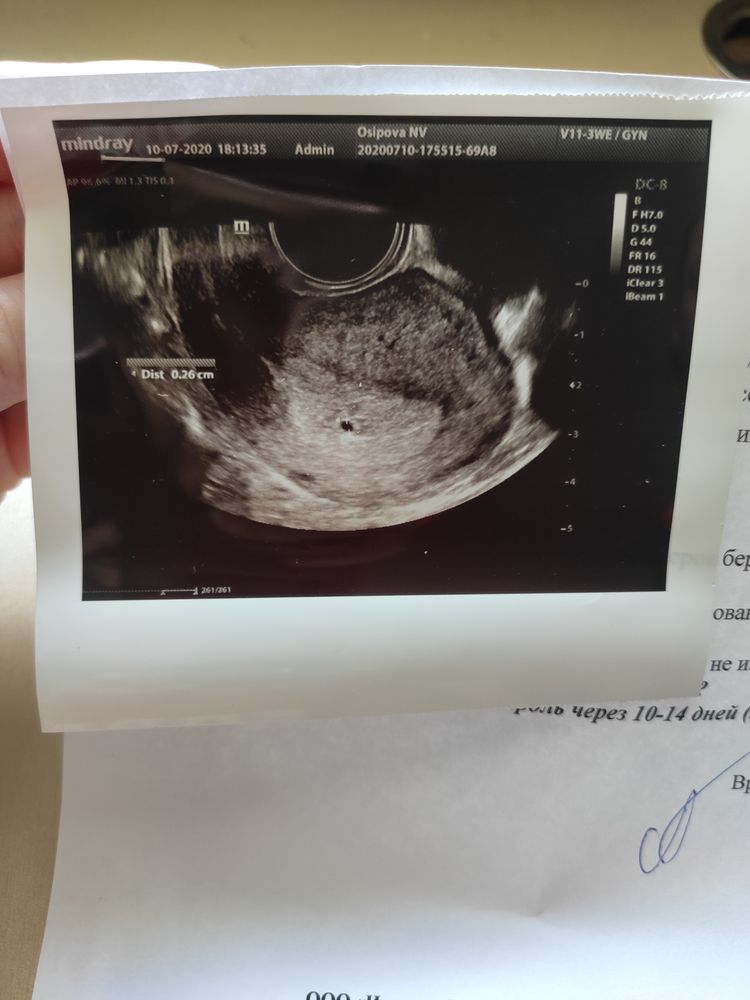

10 июля ( 5 день задержки) - еду на УЗИ ( кстати на УЗИ езжу к одному врачу уже более 5 лет, она наблюдала меня в беременность с дочей. Очень приятно, когда налажен личный контакт, уже в коридоре тебя встречают и обращаются по имени). Ну что, она посмеялась надо мной, что я прибежала так рано...Нашли по узи маленькую горошинку 2,6 мм, ЖТ 16*20 мм. Договорились встретиться через 2 недели для отслеживания динамики.